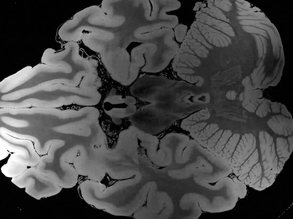

Bloody Brains